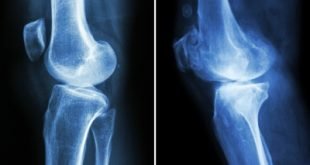

farmasetika.com – Osteporosis atau yang lebih dikenal dengan pengeroposan tulang merupakan keadaan terjadinya penurunan kepadataan tulang sehingga tulang akan keropos bahkan bisa menyebabkan patah (fraktur).  Banyak faktor penyebab terjadinya osteoporosis yaitu usia, menopause, konsumsi alkohol, masalah hormonal, kurangnya asupan kalsium dan lainnya. Jika dibandingkan dengan pria, penelitian dari International Osteporosis …

Farmasetika.com – Pada 28 April 2017, abaloparatid (Nama dagang: TYMLOS™) menerima persetujuan dari Food and Drug Administration (FDA) untuk pengobatan wanita pascamenopause dengan osteoporosis berisiko tinggi mengalami patah tulang. Apa itu osteoporosis? Osteoporosis adalah penipisan dan pengeroposan tulang. Osteoporosis biasanya terjadi pada wanita yang sudah menopause. Osteoporosis dapat meningkatkan resiko …

farmasetika.com – Sebuah penelitian yang dilakukan oleh para ilmuwan di Imperial College London telah menemukan bahwa obat yang digunakan untuk mengobati osteoporosis yang menderita kelemahan tulang (weakened bones) sebenarnya berpotensi menyebabkan kerusakan lebih lanjut. Penggunaan jangka panjang obat osteoporosis ditemukan dapat mengganggu kemampuan tubuh untuk mengganti tulang lama dengan yang lebih baru dimana memiliki jaringan …